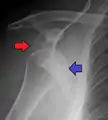

| Anterior dislocation of the left shoulder. | |

In over 95% of shoulder dislocations, the humerus is displaced anteriorly.[7] In most of those, the head of the humerus comes to rest under the coracoid process, referred to as sub-coracoid dislocation. Sub-glenoid, subclavicular, and, very rarely, intrathoracic or retroperitoneal dislocations may also occur.[8]

Anterior dislocations are usually caused by a direct blow to, or fall on, an outstretched arm. The person typically holds his/her arm externally rotated and slightly abducted.